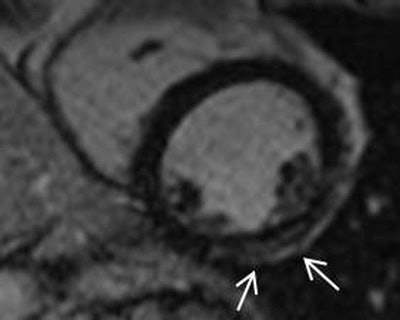

The results showed abnormalities in all 15 patients, including decreased LV end-diastolic volumes, and increased LV end-systolic volumes. There were also decreased ejection fraction measurements. Late gadolinium enhancement, mainly midmyocardial inferolateral, was found in 60% of the patients, Schelhorn said.

There was LV noncompaction in 13% of carriers (apically accented), and regional hypokinesia in 47%. There was regional myocardial thinning (more than one segment) in 80% of patients. Finally, late gadolinium enhancement was seen in 60% of patients.